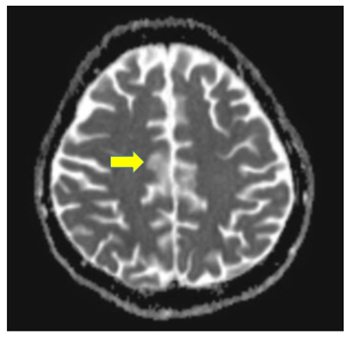

Chest condition failed to improve, a second pulse of cyclophosphamide was given followed by partial improvement of chest condition regarding ventilation parameters and radiology (x-ray). High resolution CT (HRCT) chest was requested, during transferring the patient to CT room, she developed sudden attack of hemoptysis associated with sudden worsening of her chest x-ray. Urgent bronchoscopy was done and revealed alveolar hemorrhage. Plasmaphereses was initiated and combined with ultrafiltration. After 3 sessions of plasmapheresis marvelous clinical recovery was noted, patient urine output started to improve with satisfactory levels, her creatinine dropped to 1.6 mg/dl without hemodialysis. Her chest x-ray improved, patient oxygenation and ventilation parameters improved and successfully weaned from mechanical ventilation. Patient was transferred to the ward, after 5 days from the last cyclophosphamide pulse she developed sudden grand male fits, magnetic reasoning image brain (MRI) revealed picture coop with lupus cerebritis (Figure 3). The 3rd dose of cyclophosphamide was given and she was discharged home with improved condition to be maintained on mycophenolate mofetil 500 mg every 12 hours plus 40 mg prednisolone oral with plan of weaning in the following months according to her general condition.

Figure 3 Brain MRI: picture coop with lupus cerebritis.